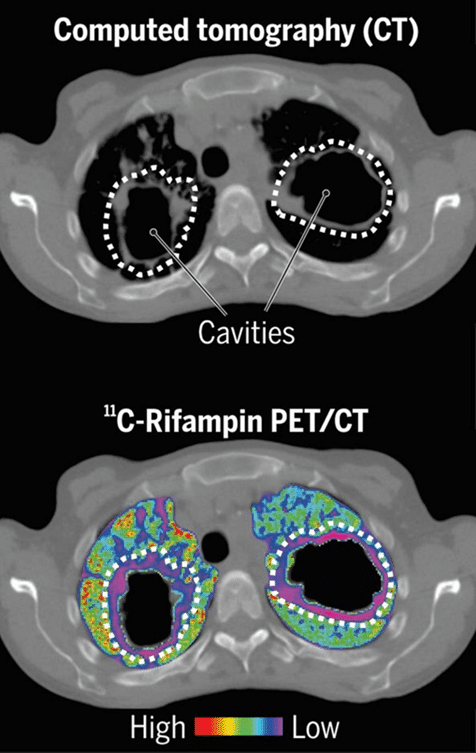

The CT scan at the top reveals the location of two lung cavities, while the bottom PET/CT image shows the failure of a radioactively tagged anti-tb drug (shown as colors) to get inside those cavities and attack the microbes they cover

Drug-Resistant Tuberculosis (DR-TB) is a form of tuberculosis resistant to one or more drugs commonly used, such as isoniazid and rifampicin. It is a serious global health problem because it is more challenging to treat. It can be caused by several factors, including improper treatment of TB, inadequate treatment regimens, and the emergence of M. tuberculosis strains with innate resistance to certain drugs.

RR-TB refers to a type of tuberculosis resistant to rifampicin treatment. This resistance can be detected through genetic or laboratory testing and may or may not be accompanied by resistance to other first-line TB drugs. WHO suggests the use of the 6-month treatment regimen composed of bedaquiline, pretomanid, linezolid, and moxifloxacin (BPaLM) rather than 9-month or longer (18-month) regimens in RR-TB patients.